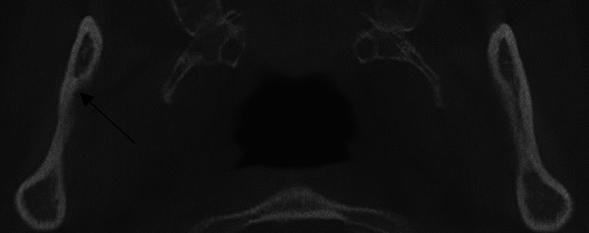

This study aims to determine whether and how the data of the medial sigmoid depression (MSD) area via cone beam computed tomography (CBCT) differs from panoramic radiography. This study also aims to evaluate various sigmoid notch types and assess the relationship between sigmoid depression and notch morphology. A total of 129 individuals consisting of 258 sides were evaluated. Chi-Square/Fisher Exact tests were used to assess parameters on a categorical scale between two or more groups. McNemar's test compared the findings detected on panoramic and CBCT images. MSD was more prevalent in females than males in both techniques, but this difference was not statistically significant. There was no association between the prevalence of MSD and the morphology of the sigmoid notch. The incidence of MSD shape was not significantly different between both imaging modalities. In both panoramic and CBCT, we found a high and similar prevalence of MSD. While the MSD prevalence was 66.7% for CBCT, it was 58.1% for panoramic. The shape or prevalence of MSDs in either approach did not correlate with sigmoid notch morphology. The two approaches' identical prevalence indicates that the panoramic image has adequately defines MSD. The high prevalence of MSD demonstrated how important it is for clinicians to characterize this anatomical variation accurately for the surgical treatment.

本研究旨在确定通过锥形束计算机断层扫描(CBCT)获得的乙状窦中嵴(MSD)区域的数据是否以及如何与曲面体层摄影术(panoramic radiography)不同。本研究还旨在评估各种乙状窦切迹类型,并评估 MSD 与切迹形态之间的关系。共评估了 129 名个体的 258 侧。使用卡方检验/Fisher 精确检验评估两个或多个组之间分类尺度上的参数。McNemar 检验比较了曲面体层摄影术和 CBCT 图像上的检测结果。在两种技术中,MSD 在女性中比男性更为常见,但这种差异无统计学意义。MSD 的患病率与乙状窦切迹的形态之间没有关联。两种成像方式的 MSD 形态发生率无显著差异。在曲面体层摄影术和 CBCT 中,我们都发现 MSD 的高且相似的患病率。CBCT 中 MSD 的患病率为 66.7%,曲面体层摄影术为 58.1%。无论哪种方法,MSD 的形状或患病率都与乙状窦切迹形态无关。两种方法的相同患病率表明,曲面体层摄影术足以定义 MSD。MSD 的高患病率表明,临床医生在手术治疗中准确描述这种解剖变异非常重要。